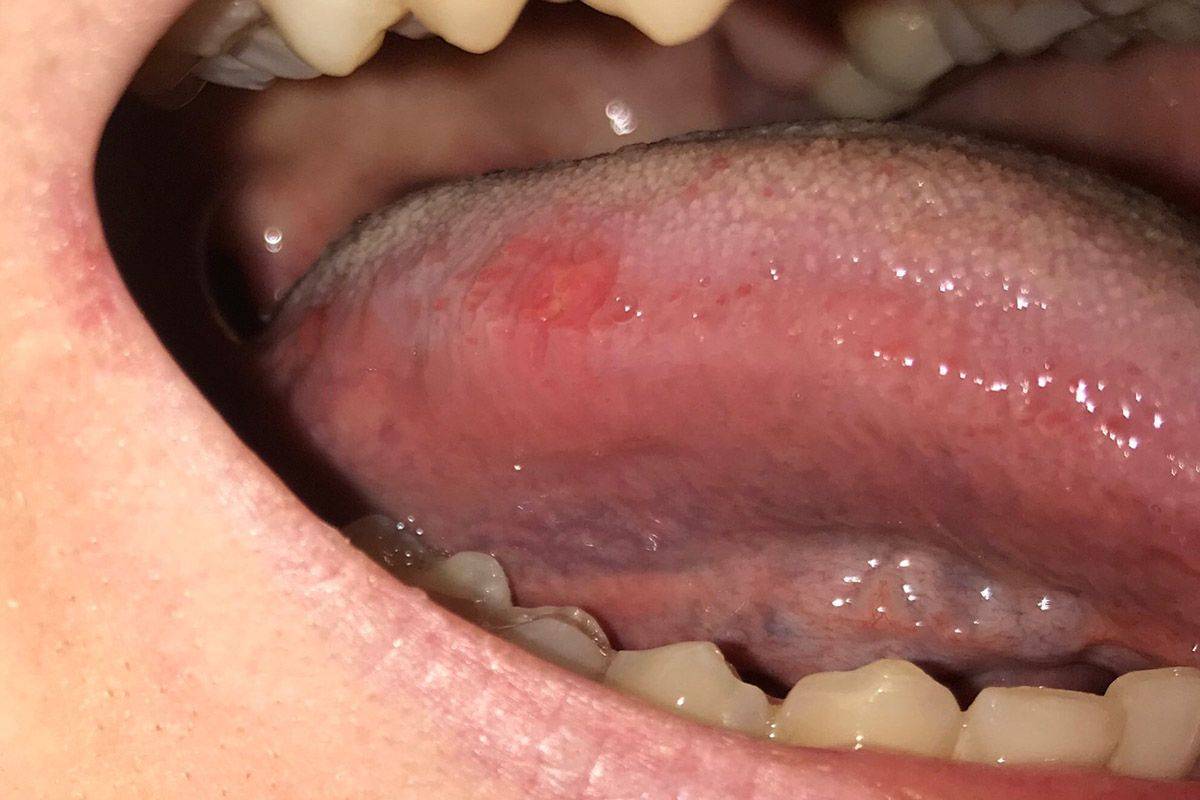

Рецивирующий афтозный стоматит. Изнуряющий хронический воспалительный процесс с эпизодическим появлением афтозных элементов (маленьких язв) на слизистой оболочке рта. Их можно увидеть на небе, губах и щеках изнутри, языке. Афты болезненны и при со временем трансформируются в плохо заживающие рубцующиеся язвы. Заболевание часто протекает на фоне инфекционной аллергии и болезней крови (например, нейтропении). Стоматит без осложнений проходит примерно за неделю. В более тяжелых случаях заживление может затянуться до нескольких недель.

Что такое стоматит – это заболевание, которое проявляется появлением на слизистой оболочке полости рта – на языке, стоматит на губах, щеках, небе – «пузырей», небольших язв во рту, ранок, афт, язвочек, вавок, эрозий и других не менее неприятных и болезненных новообразований.

Фото – стоматит во рту у взрослого человека, трещины на языке.

На фотографии – как выглядит афтозный стоматит на губе.